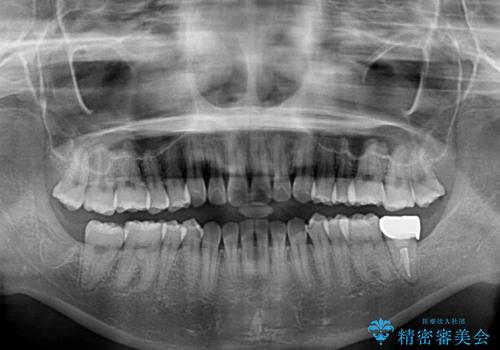

- 矯正治療の後戻りを気にして来院された患者様です。

後戻りは軽微でしたが、舌突出癖が認められ、初診時には上下前歯に舌がはまるスペースができていました。

舌突出癖の改善を行いながら、インビザライン・ライトにより矯正治療を行うこととしました。

舌突出癖の改善により上下前歯が接触するようになり、前歯でものを咬みきる必要のある食事がスムーズに行えるようになりました。